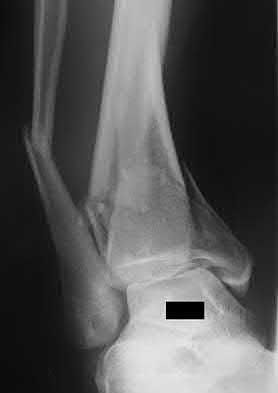

2. # A 35-year-old woman is involved in a head-on collision while driving. Initial radiographs are shown in Figures 8a and 8b. Injury to what vessel increases the risk for osteonecrosis of the injured bone?

1. Dorsalis pedis artery

2. Perforating peroneal artery

3. Lateral tarsal artery

4. Artery of the tarsal canal

5. Artery of the tarsal sinus Corrent answer: 4

The patient has a Hawkins type III talar neck fracture-dislocation with a risk of osteonecrosis ranging from 69% to 100%. Anatomic studies have shown that the artery of the tarsal canal supplies the lateral two thirds of the talar body.

The other vessels listed provide no significant contribution to the talus.